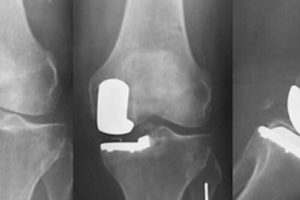

Нова методика ендопротезування

Медики Ізраїлю відкрили нові перспективи в мінімально-інвазивної хірургії. Накопичення досвіду у сфері інноваційної медицини для роботи лікарів на першому місці. Тому такі операції проводяться ортопедами не один раз в …